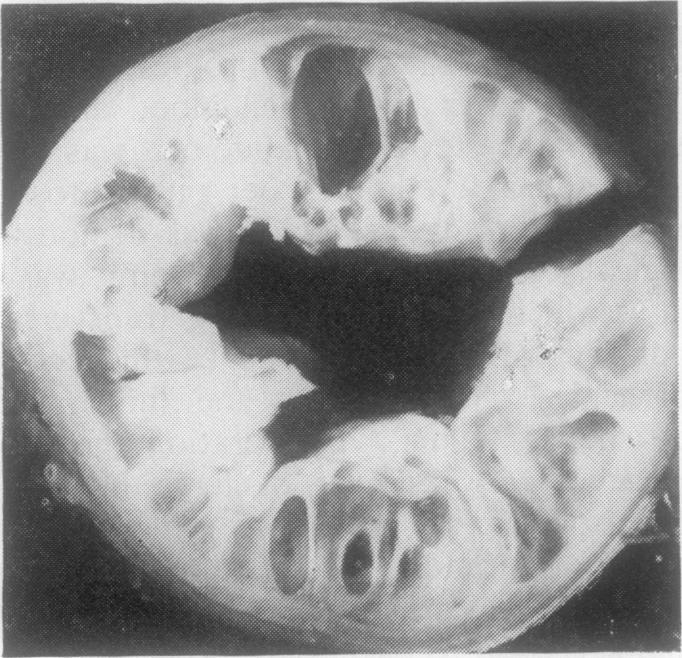

Five cases of neonatal necrotising enterocolitis occurred in full-term infants at Kingston Hospital in the space of 15 months. In all cases only the colon was involved. The pathological findings are discussed particularly in relation to the aetiology of the disease.